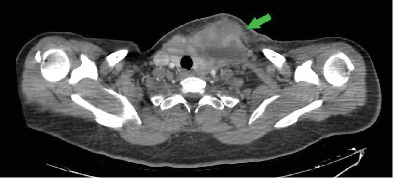

This case report discusses a rare instance of acute granulomatous thyroiditis resulting from brucellosis. A 47-year-old female cattle farmer presented with painful neck swelling and systemic symptoms. Initial investigations suggested a potential malignancy, but further testing, such as serological tests, pathology and imaging revealed brucellosis as the underlying cause. The patient underwent surgical intervention for abscess drainage and antibiotic therapy for brucellosis and showed significant clinical improvement. This case underscores the need for awareness of Brucella melitensis, a zoonotic infection, as a differential diagnosis in thyroid conditions, contributing to the understanding of its varied manifestations and complications, especially in endemic regions.